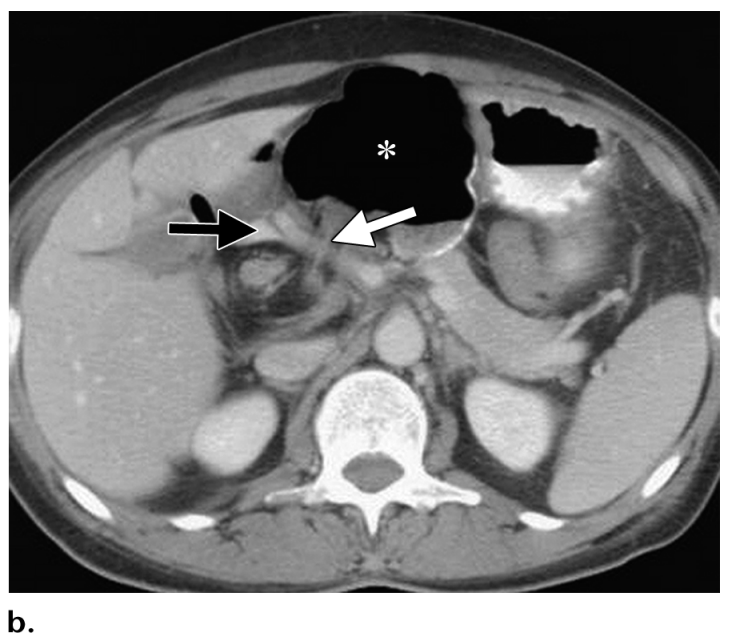

Foramen of Winslow Hernia

Axial CT image obtained in a 48-year-old woman shows the cecum (*) adjacent to the stomach, an unusual position, and passage of the right colic vessels (white arrow) across the foramen of Winslow, findings indicative of a foramen of Winslow hernia.

The foramen is marked posteriorly by the hepatic vessels (black arrow).

The presence of a foramen of Winslow hernia was confirmed at surgery.